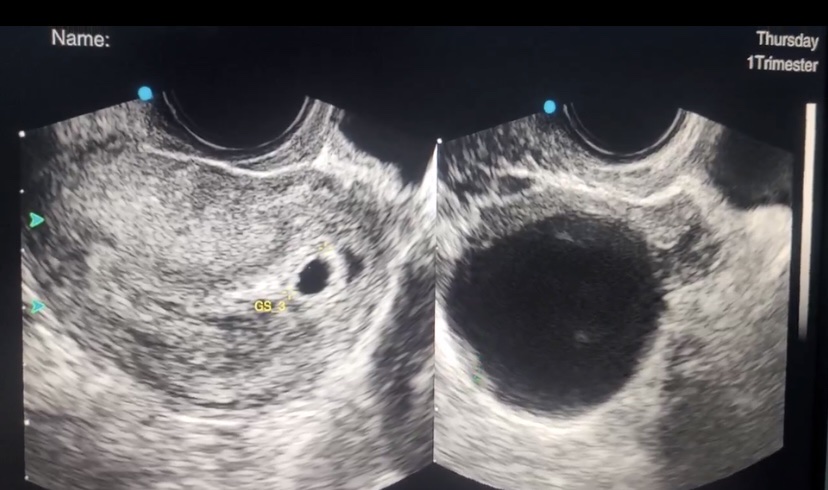

Khám phụ khoa là kiểm tra sự bất thường của âm hộ, âm đạo, cổ tử cung, buồng trứng dựa vào khám lâm sàng, siêu âm phụ khoa, xét nghiệm máu, xét nghiệm dịch âm đạo từ đó phát hiện bệnh lý phụ khoa như viêm âm đạo, nấm âm đạo, rối loạn kinh nguyệt, viêm cổ tử cung, u nang buồng trứng, u xơ tử cung, lạc nội mạc tử cung, có thai, thai ngoài tử cung, sùi mào gà sinh dục, mụn nước sinh dục, vv… Từ đó có hướng điều trị sớm, tiết kiệm được chi phí.

- Khám phụ khoa để kiểm tra có thai hay không.

Khám phụ khoa bao gồm: khám phụ khoa, siêu âm phụ khoa, xét nghiệm máu, dịch âm đạo, một số xét nghiệm tầm soát ung thư, gói khám chuyên sâu.

- Phí siêu âm phụ khoa: 170.000 – 270.000 đồng tùy theo loại, tùy bệnh viện, phòng khám.